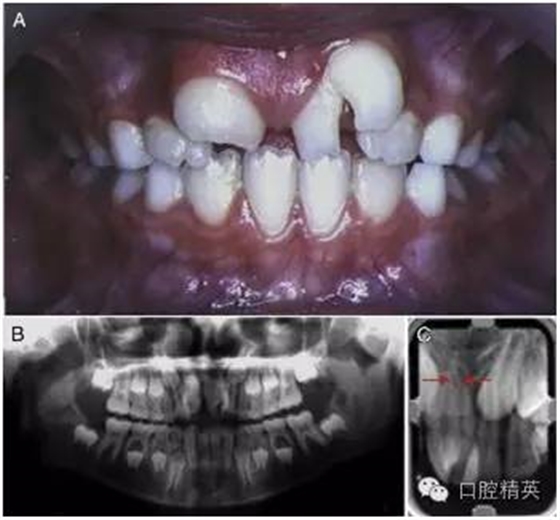

2002 年,一位左上中切牙巨大的 9 歲女孩因抱怨美觀問題而被轉診過來(圖 1)。經(jīng)初步檢查,患者口腔中剩余的其他乳牙與恒牙大小和形狀都表現(xiàn)正常,牙齒數(shù)量上無減少。患者家族史與既往病史不詳。

圖 1 左上巨牙癥術前資料。(A)口內正面像。(B)x 線全景片。(C)根尖片,箭頭所指處表明兩顆牙齒的根管影像是分開的。

進一步檢查發(fā)現(xiàn),一顆形狀不規(guī)則的多生牙與左上中切牙在冠部頸 1/3 處融合在了一起。然而,通過全景片與根尖片可以判斷出兩顆牙的根管影像是各自分開的 (圖 1-B,1-C[ 箭頭處])。這可以被認為是一條垂直向的發(fā)育溝把牙冠從近中 1/3 處分成兩個錐形牙冠造成的并生。患牙牙冠近遠中總寬度為 15mm,而正常的右上中切牙牙冠近遠中寬度只有 10mm。

由此造成的切牙區(qū)域的擁擠導致了融合牙遠中部分的唇傾(作為整體來描述則是遠中頰側扭轉)。對融合牙用冷測法進行牙髓溫度測試,測試結果為正常。

根據(jù) x 線片,可以清楚地觀察到兩個明顯的牙根因融合的牙骨質連在了一起。結合口內臨床檢查可以確定,這是由一顆不規(guī)則的多生牙與左上中切牙融合在一起的融合牙。檢查過程中,未發(fā)現(xiàn)牙髓與根尖周組織存在其他的異常。